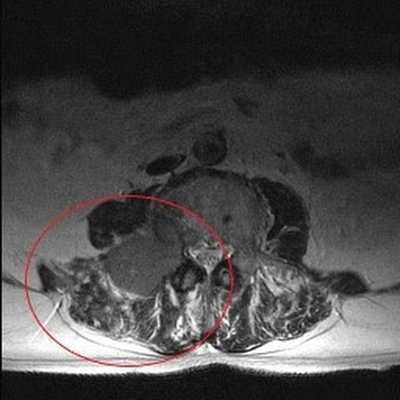

Опухолевое образование (обведено красной линией) на снимке МРТ поясничного отдела в аксиальной проекции